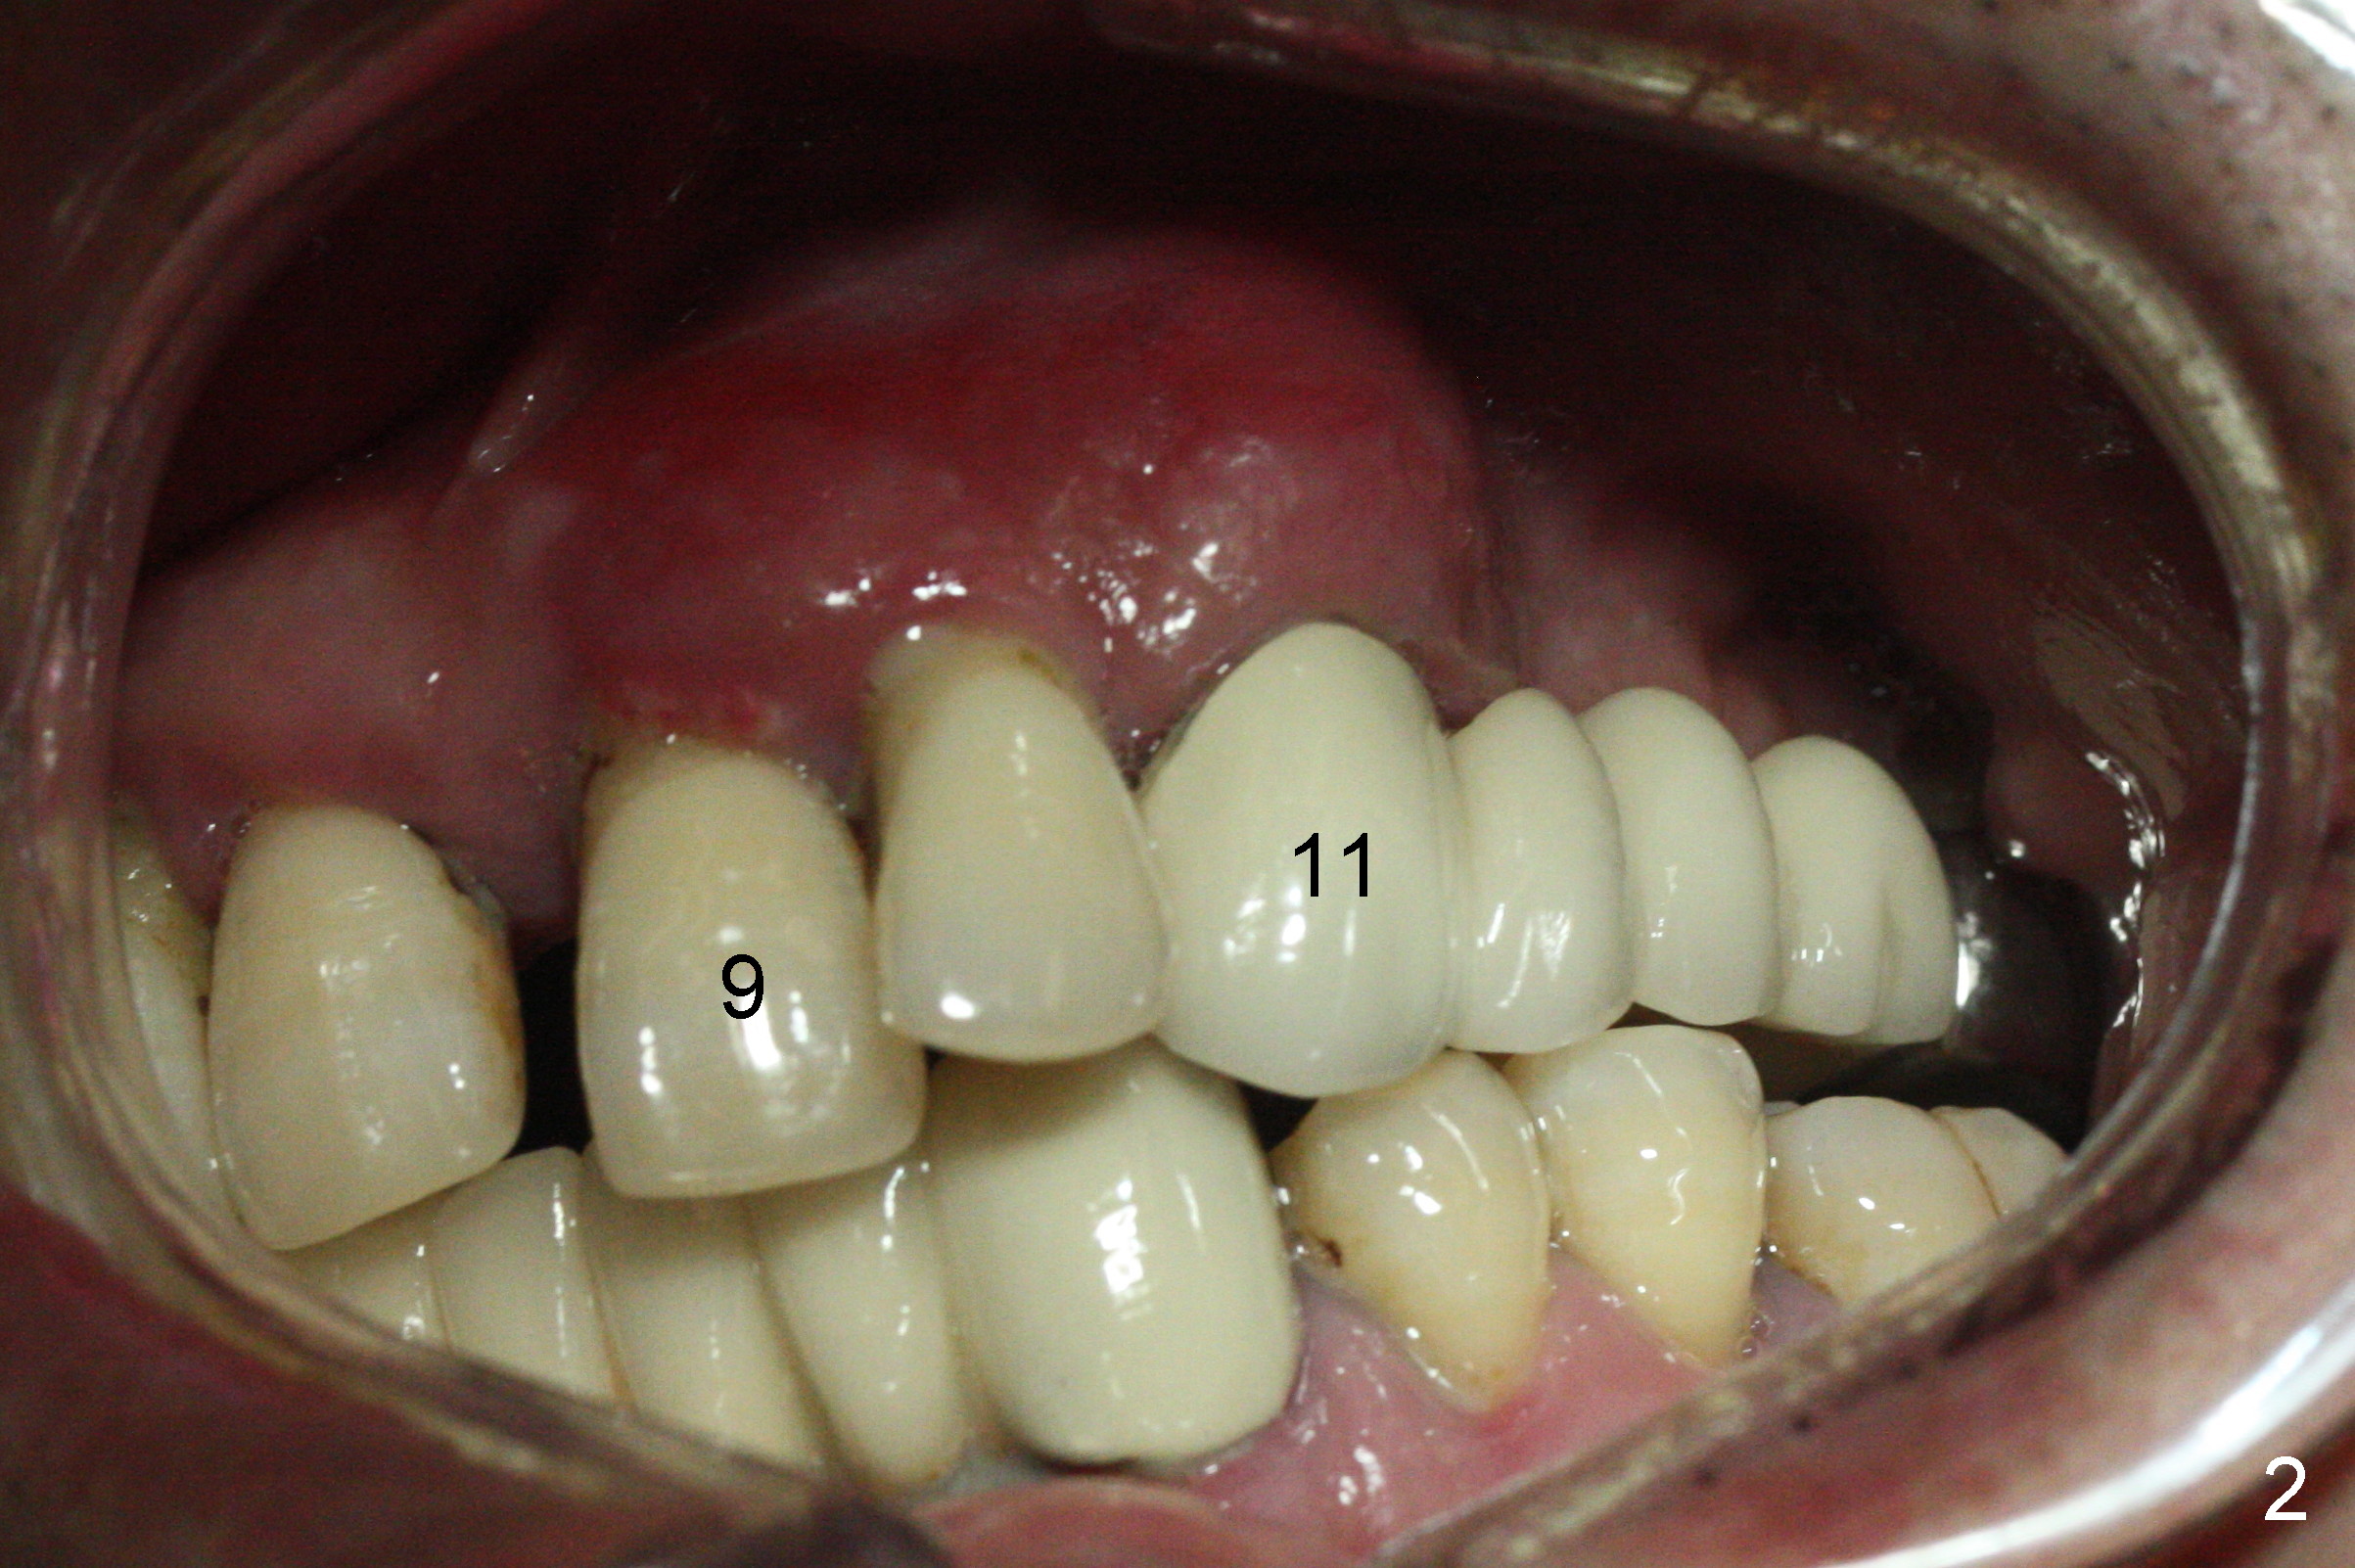

The dentition is poor except #6 and 8 (Fig.1). The gingiva is erythematous at #9-11 (Fig.2). The teeth #9 and 10 are extracted first; a 4x16 mm UF implant is placed at #9, while a 2 mm pilot drill is at the site of #10 (Fig.3). The implant at #9 is placed deeper with placement of 4.5x5.5(5) mm abutment; a 3.8x15 mm implant is placed at #10 initially (Fig.4). While the latter is placed deeper, a 4x16 mm implant is placed at #11 (Fig.5 after removal of #11-15 FPD (fixed partial denture)). In fact the trajectory at #11 is not difficult to be changed with 2 mm drill (Fig.6). After use of 3 mm drill, the implant is reinserted at #11 with ideal trajectory (Fig.7). After further seating of the implant at #11, graft is placed in the remaining sockets of #9-11 (Fig.8 *; later more graft is placed mesial to #11 implant (^)). Finally, a 4.5x7(5), 4.5x15° B (4) and 5.5x7(5) mm abutments are tightened and prepared (Fig.9) for splinted provisional at #9-10.